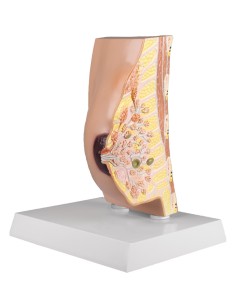

Modello per palpazione del seno, tre seni singoli su supporto - 3B Scientific L55

Modello per palpazione del seno, tre seni singoli su supporto - 3B Scientific L55